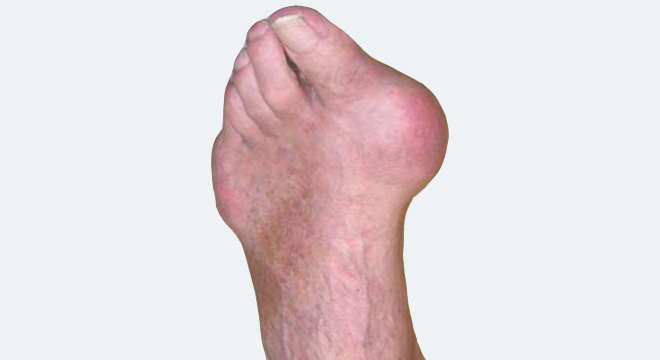

Gicht: Häufiger Befall des Grosszehengrundgelenkes

• Heftige Schmerzen, Rötung (Überwärmung), Schwellung meistens primär des Grosszehengrundgelenkes, selten des Knie- oder Sprunggelenkes